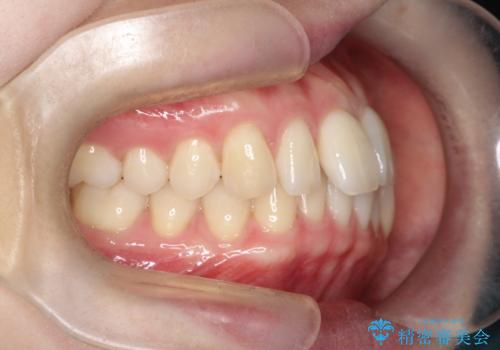

- 左上2の反対咬合(交叉咬合)をインビザラインを用いて治療しました。反対咬合は、歯列の不正咬合の一つであり、上の歯が下の歯よりも内側に位置する状態です。反対咬合は咀嚼や発音に影響を与えることがあります。

左上2の反対咬合をインビザラインで治療する際に、IPR(Interproximal Reduction)を行いました。 IPRとは、隣接する歯の間のエナメル質をわずかに削る手法で、歯の幅を減少させることによって歯列を整える技術です。